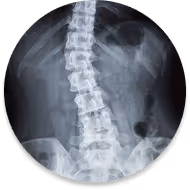

Scoliosis

Scoliosis is a sideways curvature of the spine that may develop during growth or later in life. It can cause asymmetry, stiffness, fatigue, or discomfort,and management focuses on posture, movement, and strength.